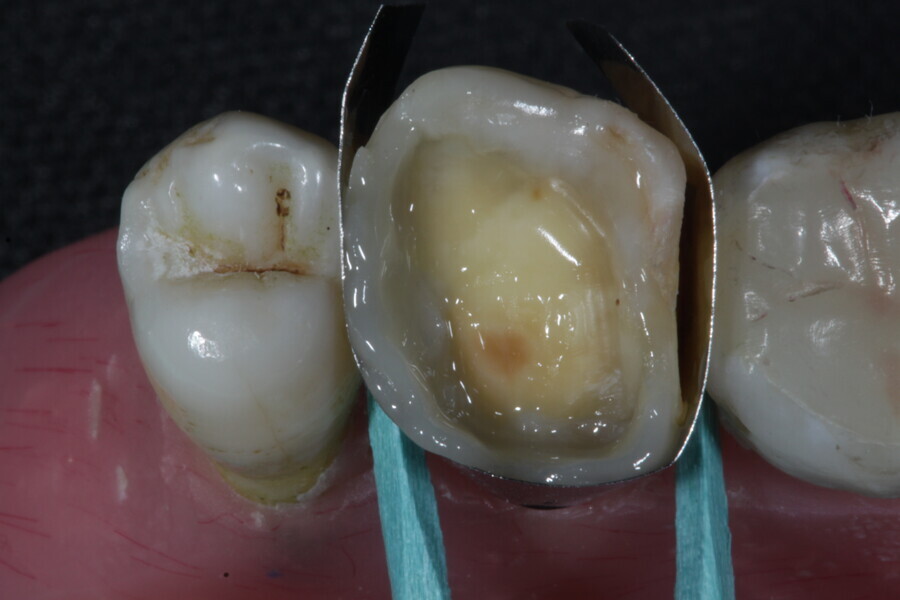

The second step focuses on reinforcing the restoration through careful fibre and FRC selection and placement. Tooth preparation should involve minimal removal of tooth structure to preserve as much natural tooth as possible in preparing the cavity for the restoration. Fibres or layers of FRC (flowable, paste, cube, etc.) are then strategically placed within the prepared tooth and composite material to reinforce areas susceptible to high stress and occlusal forces based on occlusal contact mapping. This strategic selection and placement of fibres and layers of FRC is crucial for enhancing the strength and longevity of the restoration.

1. direct restoration using a fibre-reinforced flowable composite and membrane cube after endodontic treatment (Figs. 21–35); and